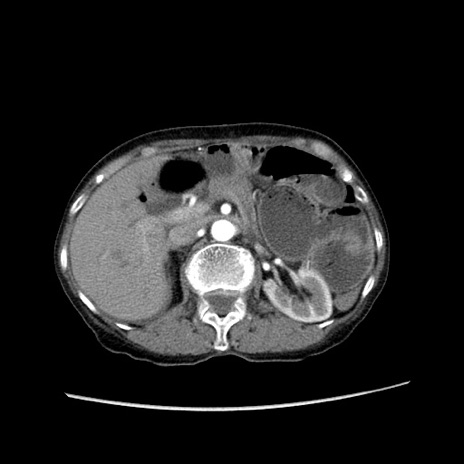

症例25(横断像)

【症例】80歳代女性

【主訴】胸のつかえ感

【現病歴】約9時間前に食後から胸のつかえた感じあり、嘔吐あり、来院。

【既往歴】胃癌(全摘)、胆摘、虫垂炎

【身体所見】心窩部に圧痛あり、反跳痛なし。

【データ】WBC 5700、CRP 0.05